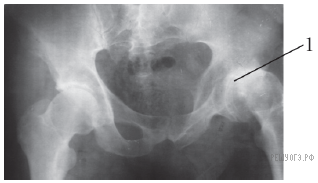

Какой сустав обозначен на рентгеновском снимке цифрой 1?

1) тазобедренный

2) голеностопный

3) локтевой

4) лучезапястный

Ответ: